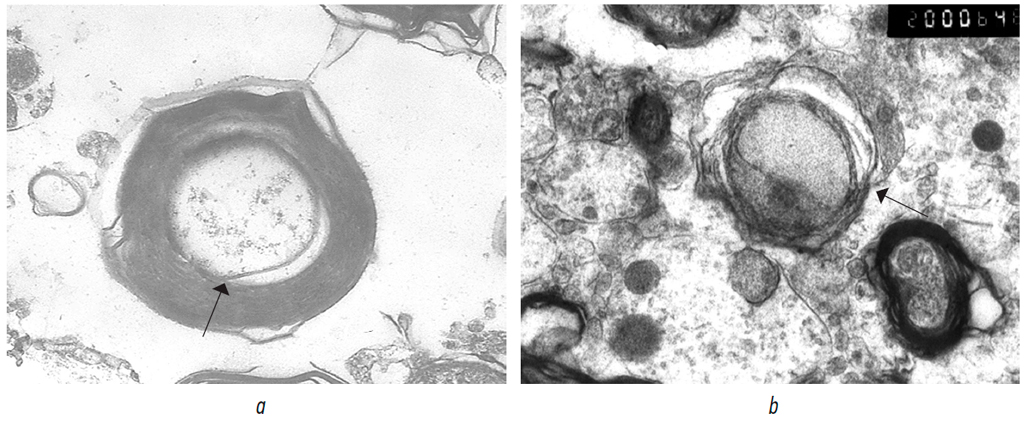

Notably, in the treatment group, 2 weeks after neurotmesis, isolated myelinated fibers in the spinal cord showed a substantial structural restoration of the myelin sheath, accompanied by moderate axonal cylinder dystrophy (axonopathy) and signs of remyelination (Fig. 9, a, b).

Fig. 9. Myelinated fibers with remyelination patterns: a — due to the inner mesaxon leaflet. ×15,000; b — due to the outer mesaxon leaflet (in the center of the image), ×20,000. The arrow indicates the area of the onset of remyelination in both images.

Рис. 9. Миелиновые волокна с признаками ремиелинизации: а — за счет внутреннего листка мезаксона, ×15 000; b — за счет наружного листка мезаксона (в центре снимка), ×20 000. Стрелкой обозначен участок начала ремиелинизации на обоих снимках.